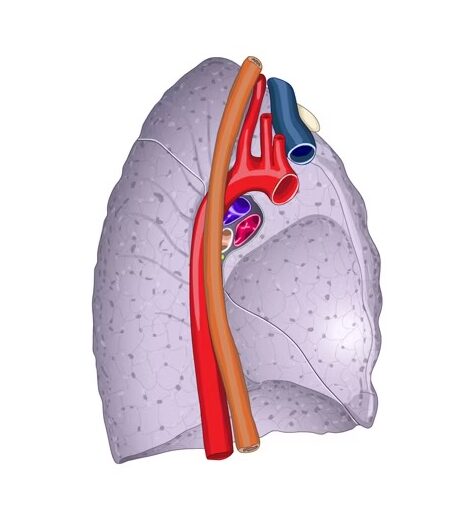

La cara mediastínica del pulmón sirve como el punto de entrada y salida para los elementos del hilio pulmonar, también conocido como la raíz pulmonar o pedículo pulmonar. Estos elementos incluyen el bronquio principal, la arteria pulmonar, las venas pulmonares y los elementos linfáticos. La presencia de estas estructuras en la cara mediastínica del pulmón es esencial para el intercambio de gases y la circulación sanguínea en el sistema respiratorio.

El hilio pulmonar es una depresión anatómica de suma importancia en el pulmón, situada en la mitad inferior de su cara mediastínica, aproximadamente en la unión de los tres cuartos anteriores con el cuarto posterior de esta cara. Su circunferencia está marcada por la reflexión de la pleura visceral sobre los elementos radiculares. Esta depresión es de vital importancia en la anatomía pulmonar, ya que es el punto de entrada y salida de los principales elementos vasculares y bronquiales del pulmón.

Además, tanto en el lado derecho como en el izquierdo, el hilio está prolongado hacia abajo y hacia atrás por la inserción del ligamento pulmonar de la pleura. Este ligamento, ubicado medialmente al pulmón (lóbulo inferior), se dirige medialmente hacia el esófago, lo que añade complejidad a la anatomía del hilio pulmonar y su relación con las estructuras mediastínicas adyacentes.